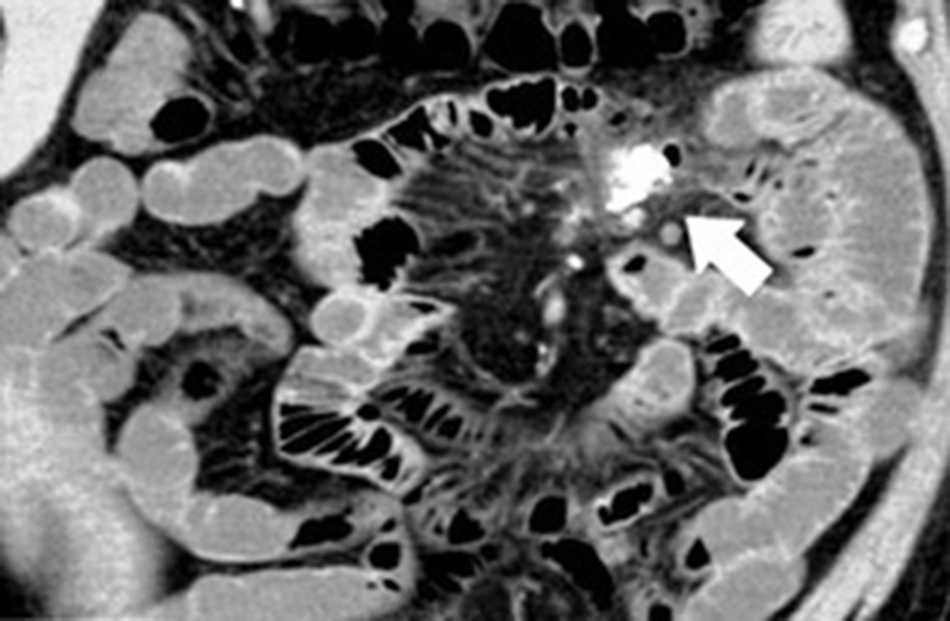

Sangrado (5%): se produce por erosión y ulceración de la mucosa en el interior del divertículo. Si bien la angiografía es el método de elección en casos de sangrado activo a fin de establecer su diagnóstico y eventual tratamiento sincrónico por vía endovascular, la TCMD muestra en la fase sin contraste restos hemáticos en su interior o signos de sangrado activo en la fase arterial1 (fig. 7).